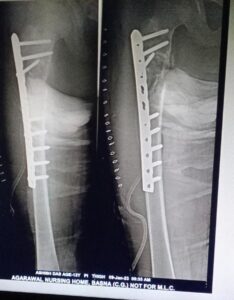

अग्रवाल नर्सिंग होम में आयुष्मान कार्ड के तहत 13 वर्षीय बच्चे का जांघ की हड्डी का हुआ निःशुल्क ऑपरेशन

बसना स्थित अग्रवाल नर्सिंग होम में डॉ. खूबचंद बघेल स्वास्थ्य सहायता योजना’ सेआशीष दास का निःशुल्क ऑपरेशन किया गया। बसना ब्लॉक के ग्राम खटखटी निवासी 13 वर्षीय मरीज आशीष दास घर में फिसल कर गिर गया था जिससे दाये जांघ की हड्डी टूट गया जिसे बसना स्थित अग्रवाल नर्सिंग होम लाये जहाँ शिशु रोग विशेषज्ञ डॉ. अमित अग्रवाल,हड्डी रोग एवं जोड़ प्रत्यारोपण विशेषज्ञ डॉ. संदीप सराफ अग्रवाल ने ऑपरेशन की सलाह दिए.

अग्रवाल नर्सिंग होम के डॉक्टर्स ने सभी आवश्यक जांच के बाद मरीज के जांघ की आधुनिक विधि द्वारा ऑपरेशन किया गया। ऑपरेशन के दूसरे दिन ही मरीज अपने पैरों पर चलने में सक्षम हो गया।